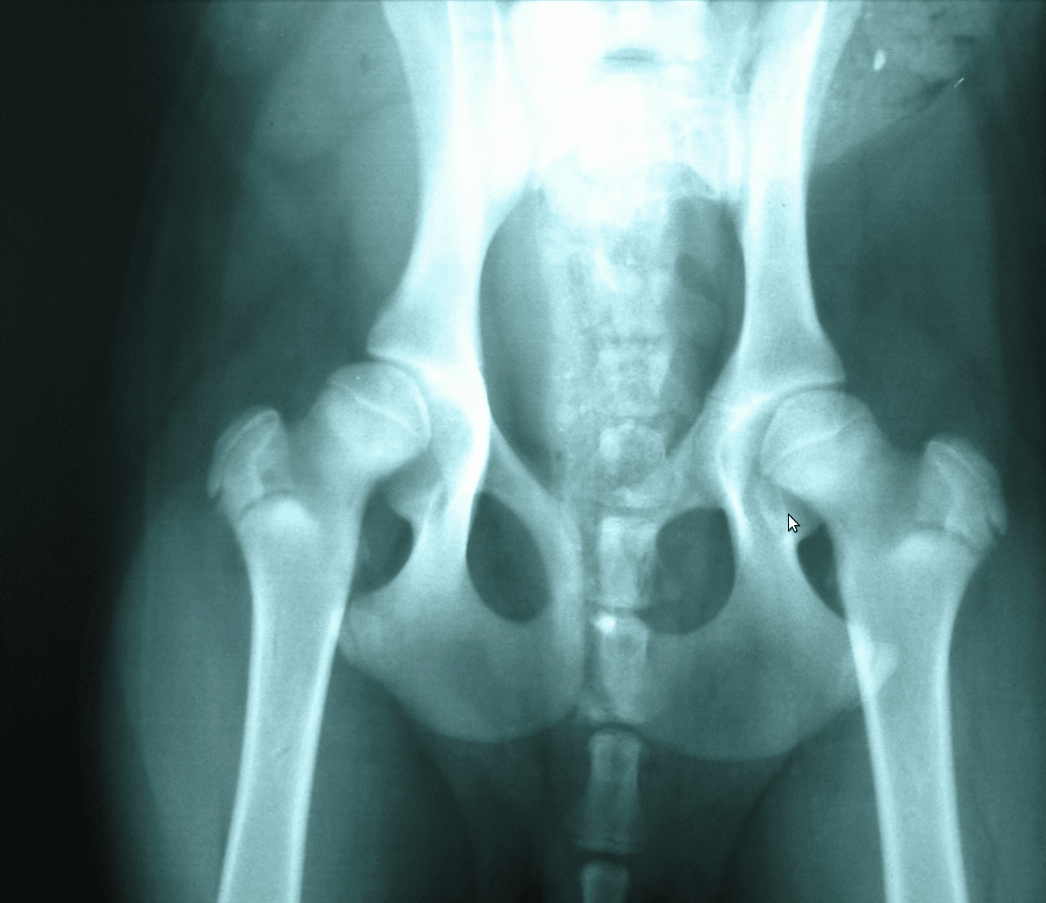

Χειρουργικές επεμβάσεις σκληρών μορίων (ενδεικτικά: κατάγματα, εξωτερική οστεοσύνθεση , ρήξη χιαστών, εξάρθρημα επιγονατίδας)